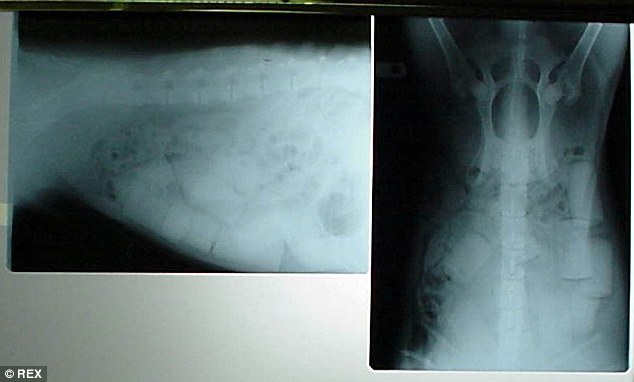

Рентгеновский снимок наркотиков, спрятанных в муле

Рентгеновский снимок лабрадора Рекса, внутри которого также пытались провести наркотики, и который скорее всего, после прохождения контроля был бы убит